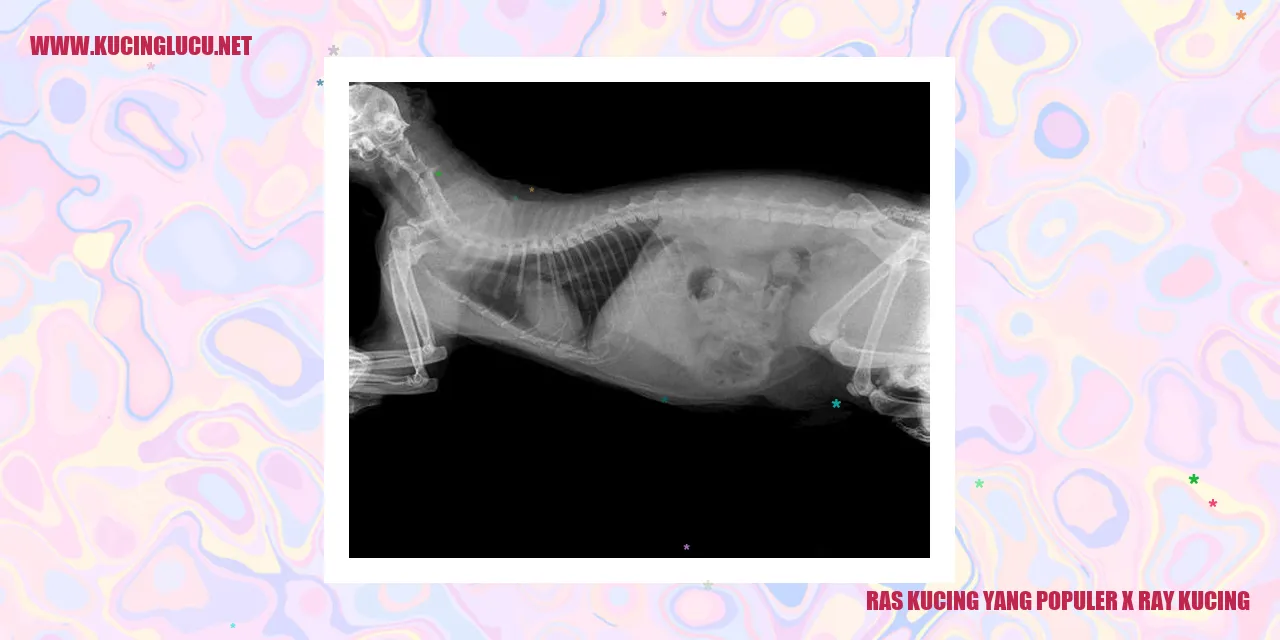

Karakteristik fisik kucing sangat beragam dan menarik. Kucing memiliki tubuh yang lincah dan gesit, dengan tulang belakang yang fleksibel. Hal ini terlihat jelas melalui penggunaan teknologi X-ray pada kucing.

X-ray kucing merupakan metode diagnostik yang menggunakan sinar-X untuk melihat struktur tubuh mereka. Dari hasil gambaran tersebut, kita dapat memperhatikan karakteristik fisik kucing yang memukau. Seperti misalnya tulang-tulang yang terbentuk dengan baik, termasuk tulang belakang yang tegak dan kuat.

Selain itu, X-ray juga memperlihatkan kelebihan tulang ekor kucing yang fleksibel dan dapat bergerak dengan lincah. Kucing juga memiliki tulang kaki yang kuat dan fleksibel, memberikan mereka stabilitas saat melompat atau berlari.

Tak hanya itu, X-ray juga memperlihatkan organ kucing seperti jantung dan paru-paru. Jantung mereka berdetak cepat, mendukung kelincahan dan kecepatan gerakan kucing. Paru-paru mereka cukup besar, memastikan mereka dapat bernafas dengan baik dan menjaga stamina saat melakukan aktivitas sehari-hari.

Karakteristik fisik kucing yang unik ini memberikan mereka kemampuan luar biasa dalam beradaptasi dengan lingkungan dan menghadapi berbagai situasi. Mereka adalah predator yang tangguh dan lincah, serta X-ray kucing mampu dengan baik menunjukkan adaptasi fisik mereka.

Secara keseluruhan, pemahaman kita tentang anatomi kucing dapat diperdalam melalui karakteristik fisik yang terlihat melalui X-ray. Kucing memiliki tubuh yang lincah, tulang belakang yang fleksibel, tulang kaki yang kuat, serta paru-paru yang besar. Semua ini memberikan keunggulan mereka dalam menjalani kehidupan yang aktif dan penuh gerakan.